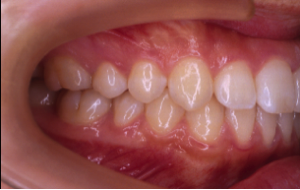

過蓋咬合(かがいこうごう)※ 非抜歯

20歳/女性

悩み:噛み合わせが深い

下の前歯が上の歯茎に食い込んでいる状態

治療期間:約2年

治療前

治療後

深い噛み合せを改善する治療が必要になりました。

先に深い噛み合せを上げないと矯正装置がつかないので、噛み合せの深さを改善する治療から行なう矯正治療となりました。